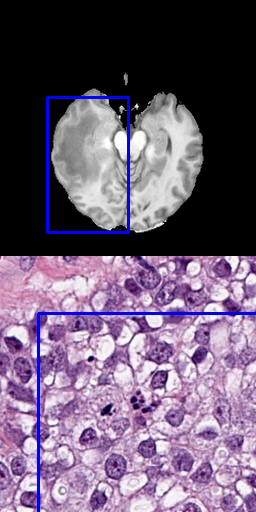

One approach is to use several positive points as input data that represent the goal label [8]. Using points as input is a precise method, allowing to preserve fine segmentation details but requires more annotation effort. When large areas are annotated, this is especially problematic. Figure 3 shows samples for using 3, 10, 50 or 100 points for the radiology and pathology data.

Refer to caption

(a) 3 positive points

(b) 10 positive points

(c) 50 positive points

(d) 100 positive points

Figure 3: Results for different number of positive points without bounding box